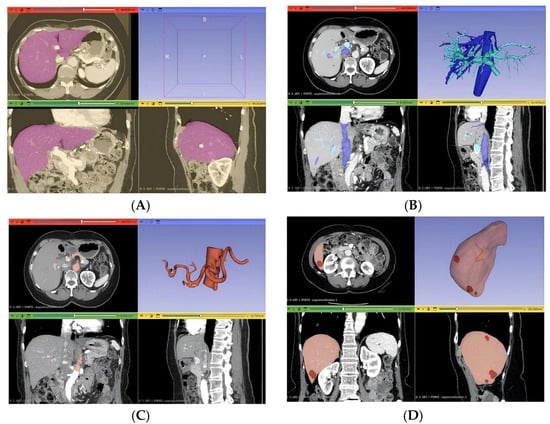

Three distinct anatomical segmentations were carried out to generate the final 3D liver model: lesion segmentation, vascular segmentation, and segmentation of the entire liver volume (Figure 3). The lesion segmentation focused on identifying three metastases, with quantitative descriptors extracted for each, including maximum 2D diameter, volume, and short-axis length. Vascular segmentation was divided into two components: one targeting the portal and hepatic veins, and the other focusing on the hepatic artery.

For the portal and hepatic veins, a threshold mask was applied within the intensity range [137.67; 1472]. Due to the presence of surrounding artifacts, an additional mask was generated using the “Keep Selected Islands” function to isolate relevant vascular structures. The “Region Growing” tool was then applied to differentiate hepatic veins from the portal vein. Hepatic artery segmentation began with a manual volume cropping to localize the arterial region, which served as a refined mask for subsequent region growth. Unrelated structures were removed, ensuring that only the hepatic artery remained. This process was performed specifically on arterial-phase CT images to enhance vascular contrast and segmentation fidelity.

Figure 3. (A) Segmentation of liver volume; (B) segmentation of the portal vein and the suprahepatic veins; (C) segmentation of the hepatic artery; (D) lesion segmentation.